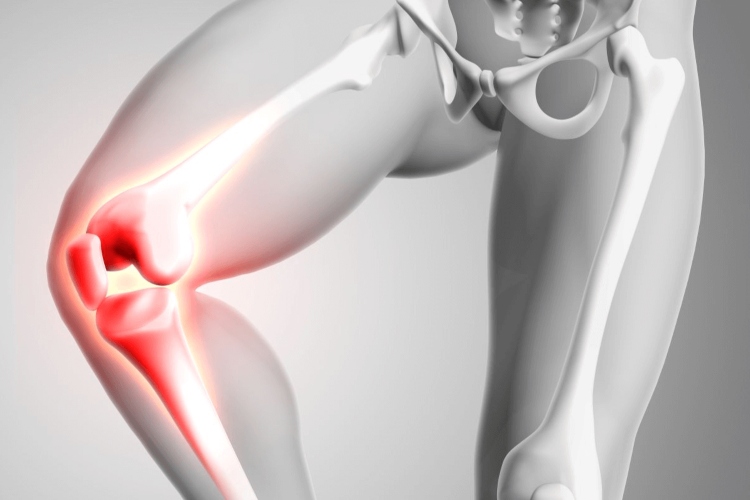

Científicos han logrado un avance revolucionario en el tratamiento de la artritis: un cartílago artificial capaz de detectar las señales de dolor y bloquearlas de manera automática. Esta innovación ofrece esperanza a millones de personas que padecen esta enfermedad degenerativa y que buscan alternativas más efectivas frente a los analgésicos tradicionales.

El material biomédico creado imita las propiedades naturales del cartílago humano, pero con una diferencia crucial: integra sensores capaces de identificar la inflamación y la presión anormal que produce dolor en las articulaciones.

Una vez detectado, el cartílago libera un bloqueo neural localizado que evita que las señales dolorosas lleguen al sistema nervioso central.

La artritis afecta la movilidad y calidad de vida de quienes la sufren. Los tratamientos actuales se centran en fármacos que reducen la inflamación o en terapias de reemplazo articular, pero con efectos secundarios significativos.